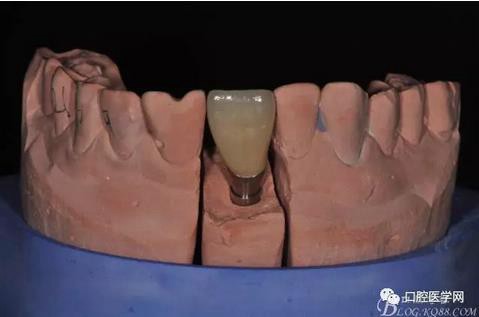

圖14 烤瓷冠模型唇側(cè)照

圖15 烤瓷冠模型舌側(cè)照

圖16 修復(fù)基臺(tái)模型頜面照